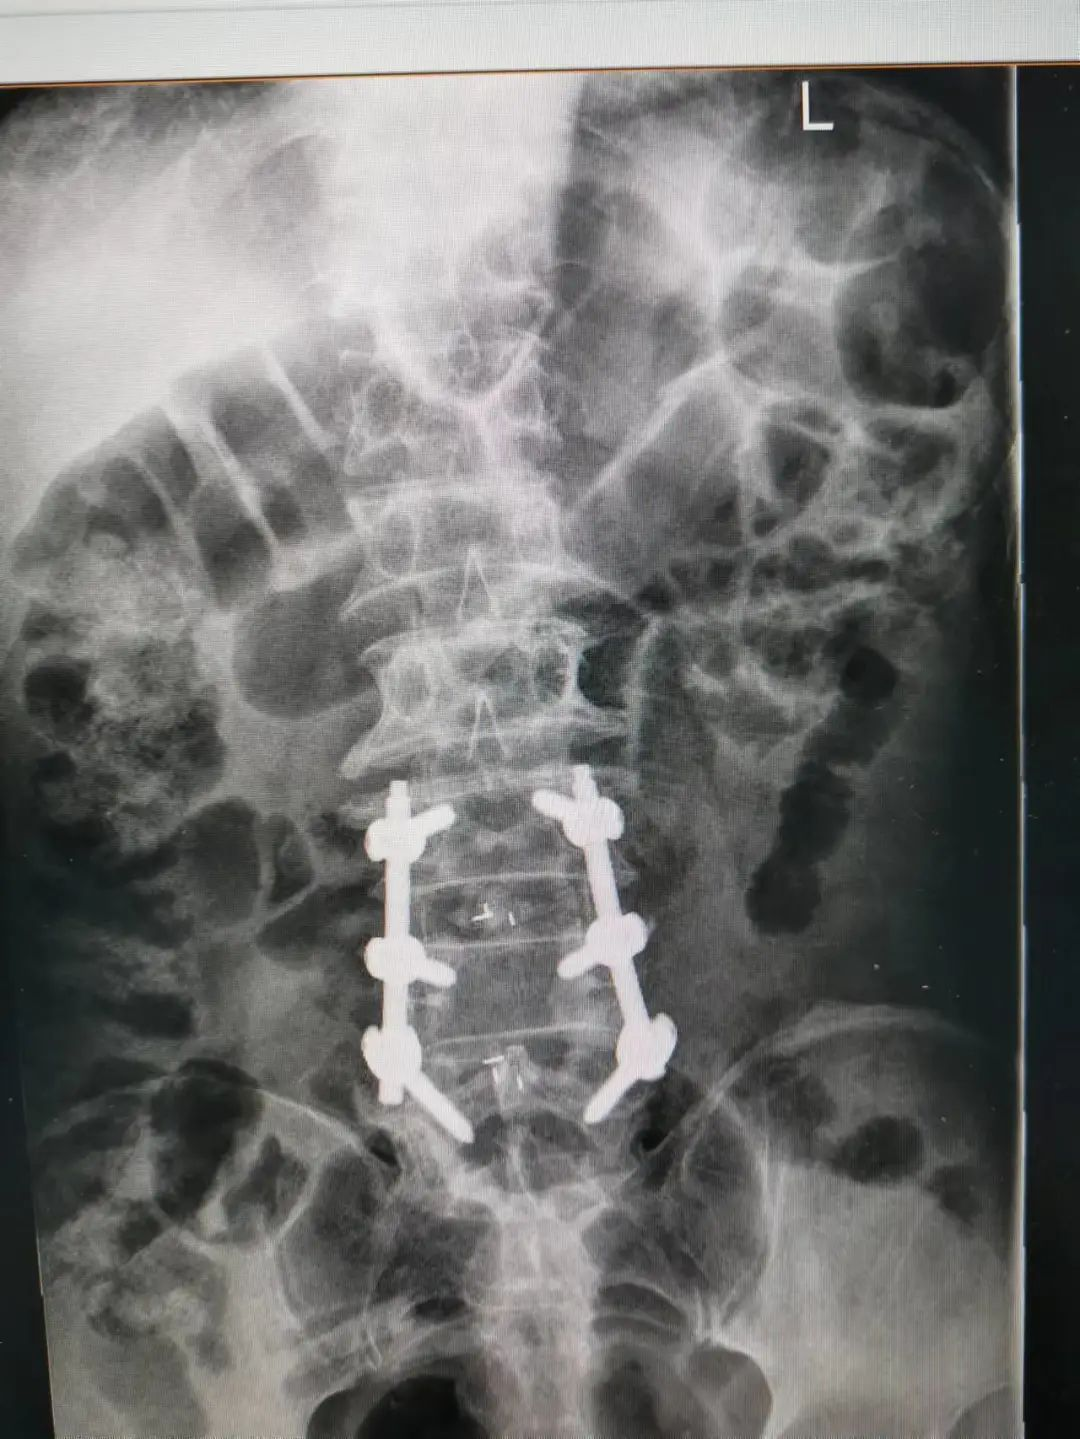

楊先生腰椎管狹窄癥拍片

由于楊先生的病情嚴(yán)重,需住院治療。楊先生入院后,瀘州市中醫(yī)醫(yī)院骨傷二科科主任楊陳一制定了手術(shù)計(jì)劃,決定脊髓型頸椎病的手術(shù)從前路切開減壓,頸3/4 、頸4/5、 頸5/6、 頸6/7椎間盤切除,椎間融合,鋼板內(nèi)固定術(shù)手術(shù),而腰椎管狹窄癥經(jīng)后路切開減壓,腰3/4、腰4/5椎同盤動(dòng)除,椎間融合、釘棒系統(tǒng)內(nèi)固定術(shù)。

楊先生術(shù)后拍片